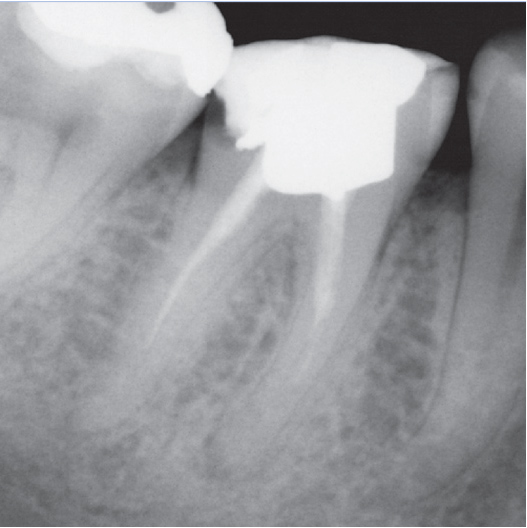

After

After Root Canal treatment